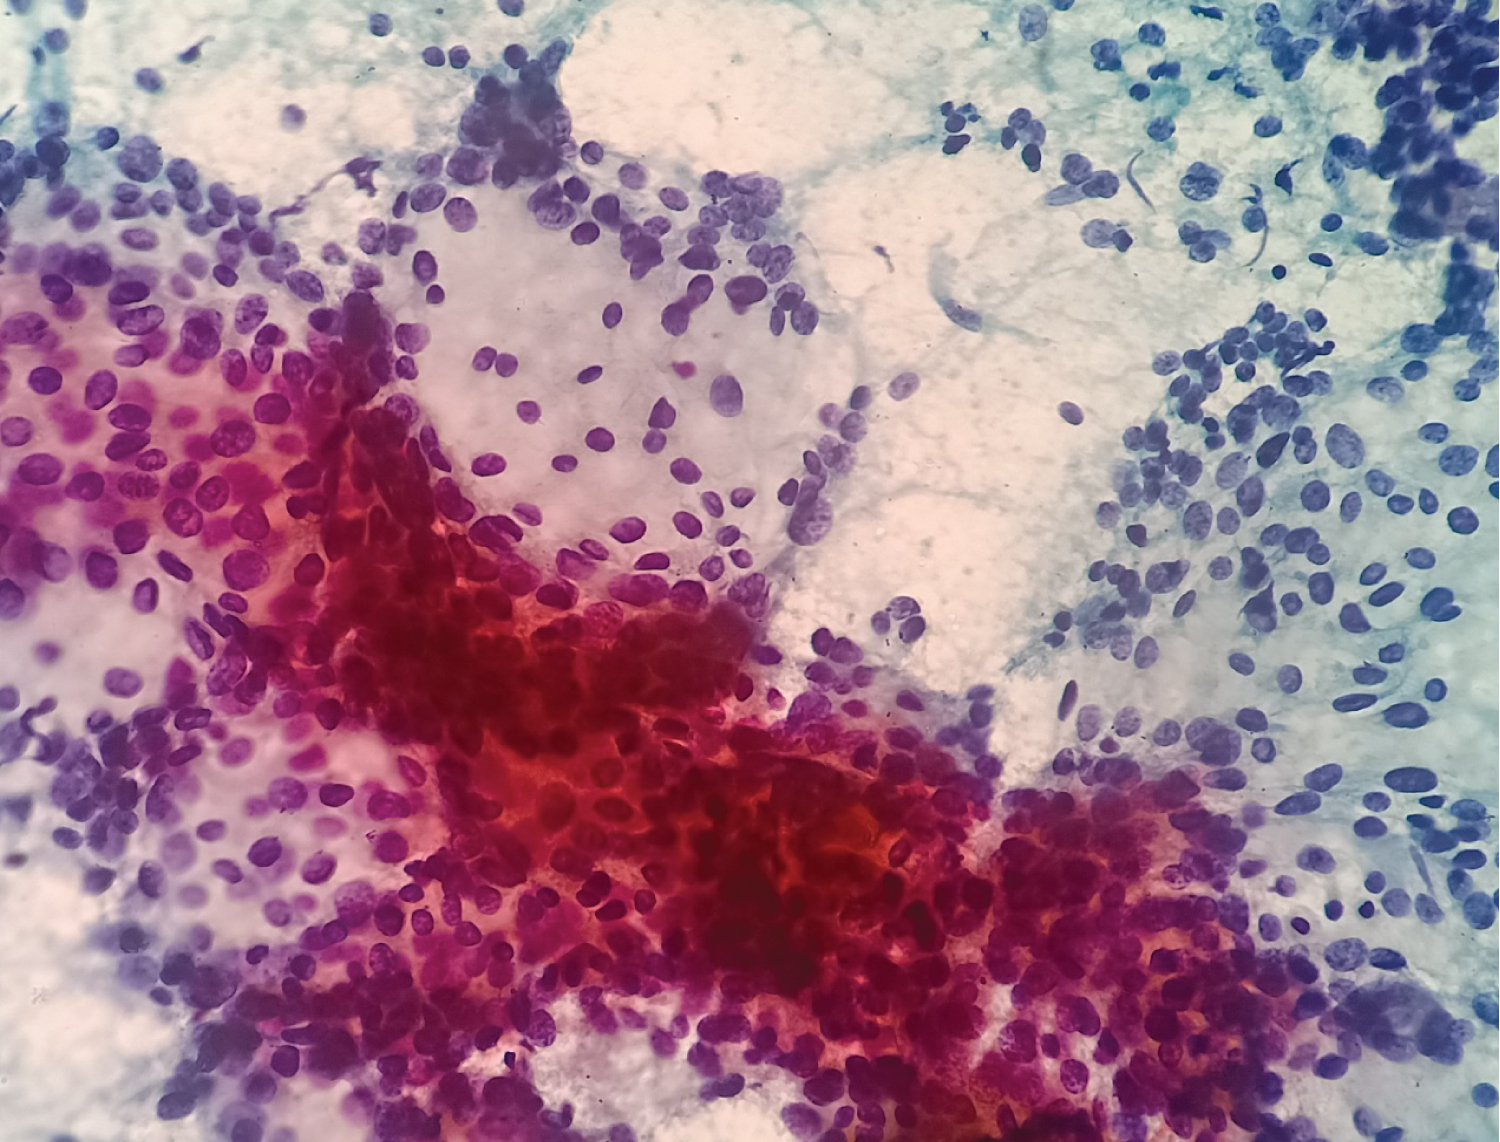

A 38-year-old female presented with the complaints of pain and difficulty during swallowing and history of weight loss. Up on examination, a swelling was noted on the left side of her neck, which moved with deglutition. Ultrasound (USG) revealed a well circumscribed hypo echoic nodule measuring 3.2 × 2.1 cm in the left lobe of thyroid with no extrathyroidal extension, however the nodule was compressing the esophagus. Fine needle aspiration was performed on the lesion and stained with Papanicolaou (PAP) stain and May Grunwald Geimsa (MGG) stains. The smears exhibited high cellularity with globoid clusters and three dimensional tissue fragments composed of aggregates of cells with central core of homogenous basement membrane material with cells having basaloid morphology and scant cytoplasm (Figure 1). MGG smears highlighted pink/ magenta amorphous basement membrane hyaline globules in the clusters of tumor cells (Figure 2). Cell block preparation of fine needle aspiration showed cribriform pattern of tumor cells with hyaline globules (Figure 3). Immunocytochemistry conducted on cell block shows TTF-1 positivity in normal thyroid follicles and negative staining in tumor cell clusters. CD117 and synaptophysin were inconclusive on cell block, but based on morphology this case was reported as adenoid cystic carcinoma of thyroid. Contrast-enhanced computed tomography (CECT) prior to surgery depicted a well defined heterogeneously enhancing hypodense lesion in the left lobe of thyroid measuring 3.2 × 2.1 × 1.7 cm with no additional lesions or abnormalities noted in the adjacent structures like trachea, larynx, oesophagus or upper mediastinum (Figure 4). The excised left hemi-thyroidectomy specimen was received which showed a grey white solid homogenous lesion measuring 3.5 × 2.2 × 2 cm reaching till the capsule. No cystic spaces/papillary projections/colloid seen in the lesion grossly. Adjacent thyroid parenchyma was normal. Histopathology sections showed tumor arranged in tubules and cribriform pattern along with hyaline globules suggesting the diagnosis of adenoid cystic carcinoma of thyroid, limited to thyroid without extrathyroid extension (Figure 5). IHC with CD117 showed cytoplasmic positivity in tumor cells further supporting the diagnosis (Figure 6).

Figure 1: Papanicoalaou stained (20x) showing globoid clusters of basaloid cells with luminal hyaline globules. View Figure 1

Figure 2: MGG stained smears (20x) showing globoid clusters of basaloid cells with luminal hyaline globules (arrow). View Figure 2